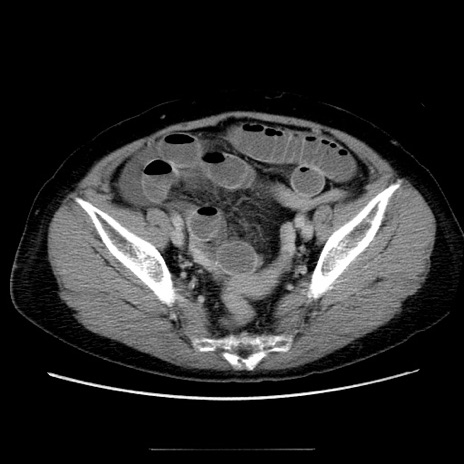

症例5(横断像)

【症例】70歳代女性

【主訴】お腹が張る

【現病歴】1週間くらい前から腹部膨満の自覚あり。昨日夜から増悪したため、本日救急外来受診。

【身体所見】意識清明、BT 36.5℃、BP 165/106mmHg、HR 80bpm、SpO2 98%、腹部:膨満、軟、自発痛・圧痛なし、触診にて不快感あり、腸蠕動音:減弱

【データ】WBC 12600、CRP 1.04